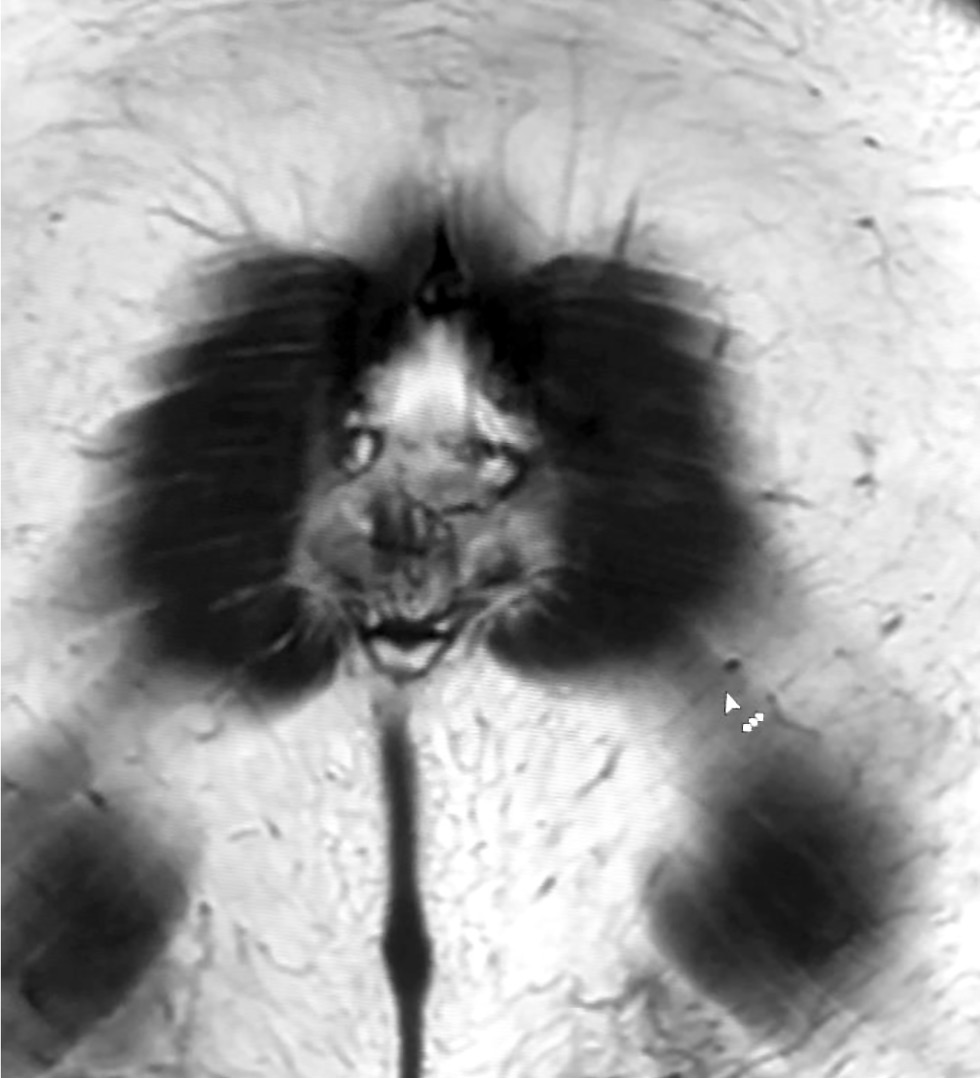

Visual images in radiography: pareidolia as a useful tool for physicians and artificial intelligence

Abstract

This article explored the role of pareidolia in radiography and its potential in improving diagnosis and medical personnel training. Pareidolia is the phenomenon of perceiving familiar patterns in random objects, such as faces on the moon’s surface and animal figures in clouds. In radiography, pareidolia can manifest as recognizable patterns in medical images. This enables radiographers to identify abnormalities and improve their diagnostic skills.

This work aimed to evaluate pareidolia caused by the interpretation of X-ray images and determine its potential applications.

From June to December 2023, a competition was held to create a dataset of pareidolic illusions. Thirty-one individuals participated, including medical imaging specialists who had access to radiographic images. Images from nine additional participants were obtained outside the competition. Overall, 71 images were received. Participants uploaded images using a form on Yandex Forms. Data quality was ensured by clearly defined inclusion and exclusion criteria.

Data analysis revealed that people most frequently perceive human faces, animal snouts, and the heart symbol. These findings indicate the possibility of further research. This article discusses the potential applications of pareidolia in developing neural networks for automated medical image analysis and in educational activities that stimulate creative thinking and association.

Moreover, the article emphasizes the importance of ongoing research in this area to develop effective diagnostic tools and educational programs by expanding the evidence base.

510-521